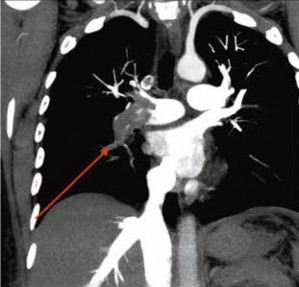

Debido al deterioro respiratorio, la paciente fue referida a un centro de mayor complejidad en la ciudad de Tacna ingresa al servicio de urgencias, al área de trauma shock con presión arterial de 98/71 mmHg; frecuencia cardiaca de 110 lpm; frecuencia respiratoria de 22 rpm; SaO2 94 % FiO2 44% Glasgow de 15 puntos. Se toma una tomografía pulmonar con contraste endovenoso (Figura 2), donde se evidencia un trombo obstructivo de la totalidad de la arteria pulmonar derecha, por lo que se diagnostica tromboembolia pulmonar masiva; la paciente presenta una convulsión tónico clínica, se coloca oxígeno con máscara de Venturi FiO2 50%, además de un catéter venoso central, luego se inicia la aplicación de vasopresores a dosis bajas.

Se define tromboembolia pulmonar masiva cuando se presenta en sujetos sin enfermedad cardiopulmonar previa con obstrucción > 50% del lecho vascular pulmonar y en aquéllos con enfermedad cardiopulmonar[10]. Nuestra paciente presentó obstrucción del 100% de la arteria pulmonar derecha (Figura 02) y de >50% de la arteria pulmonar izquierda.